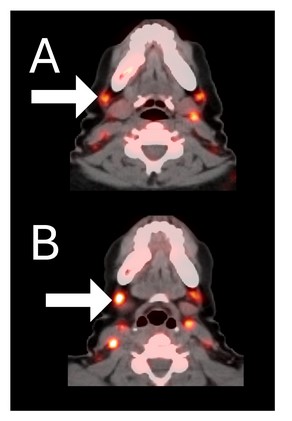

Before BriaCell Treatment Image A: CD8 ImmunoPET image

Pre-treatment imaging of cervical (neck) lymph nodes with moderate uptake indicating presence of some CD8+ cytotoxic (“killer”) T cells.

After BriaCell Treatment Image B: CD8 ImmunoPET image

Post treatment enhancement of cervical (neck) lymph nodes indicating immune system activation and increased presence of CD8+ cytotoxic T cells.

Example 2 Images (Patient 15-005): CD8 ImmunoPET images pre (A) and post (B) Bria-IMT treatment